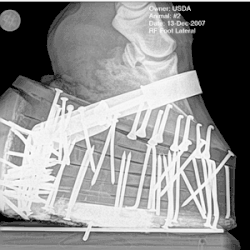

Congress delegated statutory responsibility for enforcement to the management of sales and horse shows, but placed administration of the act with the Animal and Plant Health Inspection Service (APHIS) of the United States Department of Agriculture (USDA). Violations of the HPA may result in criminal charges, fines and prison sentences. The USDA certifies certain Horse Industry Organizations (HIOs) to train and license Designated Qualified Persons (DQPs) to complete inspections. APHIS inspection teams, which include inspectors, investigators, and veterinary medical officers, also conduct unannounced inspections of some horse shows, and have the authority to revoke the license of a DQP who does not follow the standards of the Act.[29]

Soring is defined by the HPA with four meanings:

"(3)(A) an irritating or blistering agent has been applied, internally or externally, by a person to any limb of a horse, (B) any burn, cut, or laceration has been inflicted by a person on any limb of a horse, (C) any tack, nail, screw, or chemical agent has been injected by a person into or used by a person on any limb of a horse, or (D) any other substance or device has been used by a person on any limb of a horse or a person has engaged in a practice involving a horse, and, as a result of such application, infliction, injection, use, or practice, such horse suffers, or can reasonably be expected to suffer, physical pain or distress, inflammation, or lameness when walking, "[31]

Action devices, which remain legal but are often used in conjunction with illegal soring practices,[27] are defined in the Code of Federal Regulations as "any boot, collar, chain, roller, or other device which encircles or is placed upon the lower extremity of the leg of a horse in such a manner that it can either rotate around the leg, or slide up and down the leg so as to cause friction, or which can strike the hoof, coronet band or fetlock joint".[32]

Between 1978 and 1982, Auburn University conducted research as to the effect of applications of chemical and physical irritants to the legs of Tennessee Walking Horses. The study found that chains of any weight, used in combination with chemical soring, produced lesions and pain in horses. However, chains of 6 ounces or lighter, used on their own, produced no pain, tissue damage or thermographic changes.[33]

Soring can be detected by observing the horse for lameness, assessing its stance and palpating the lower legs. Some trainers trick inspectors by training horses not to react to the pain that palpation may cause, often by severely punishing the horse for flinching when the sored area is touched. The practice is sometimes called "stewarding", in reference to the horse show steward. Some trainers use topical anesthetics, which are timed to wear off before the horse goes into the show ring. Pressure shoeing is also used, eliminating use of chemicals altogether. Trainers who sore their horses have been observed leaving the show grounds when they find that the more stringent federal inspection teams are present.[35]